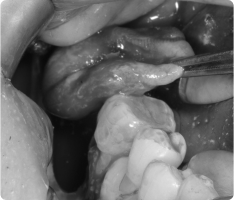

함치성 낭종은 나지 않은 치아(주로 사랑니, 송곳니) 주위에 생기는 물주머니(낭종)입니다.

치아가 잇몸 속에서 올라오지 못하고 머물면서 그 주위에 액체가 고여 발생합니다.

- 흔히 사랑니나 매복된 송곳니에서 발견됩니다.

- 크기가 커지면 주변 뼈를 흡수하거나, 옆 치아 뿌리를 밀어 손상시킬 수 있습니다.

- 대부분 통증이 없어 정기적인 X-ray 검사에서 우연히 발견되는 경우가 많습니다.

- 국소마취 후 잇몸을 열어 낭종과 함께 원인 치아를 제거합니다.

- 낭종 벽을 깨끗이 적출하여 재발을 막습니다.

- 병리검사를 통해 정확한 진단을 확인합니다.

- 작은 경우는 간단히 제거가 가능하고, 큰 경우는 단계적으로 치료하기도 합니다.